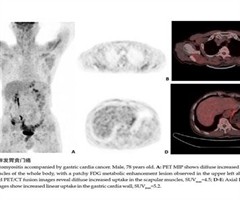

18F-FDG PET/CT显像对皮肌炎伴发恶性肿瘤具有诊断价值

摘要:目的 探讨皮肌炎伴发恶性肿瘤患者的18F-FDG PET/CT图像特点,以期提高对该病的认识。方法 回顾性分析2018年4月~2023年3月经病理确诊的14例皮肌炎伴发恶性肿瘤的患者,用手划感兴趣区法分析全身肌肉摄取程度,同时设立正常...